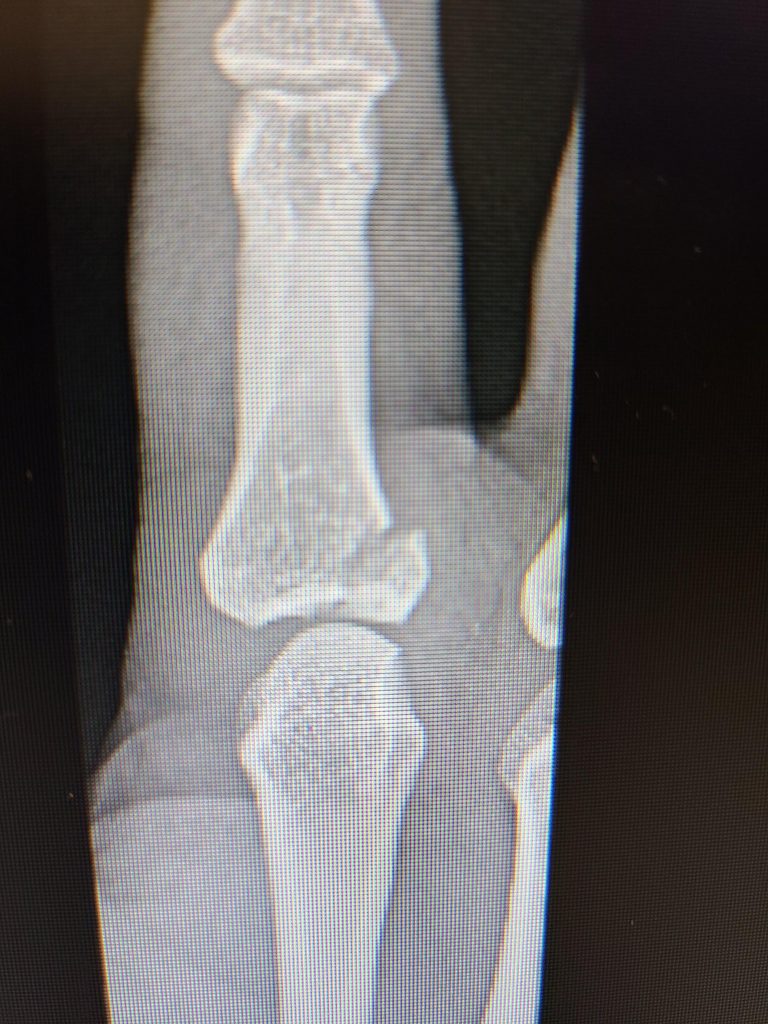

My story begins when my finger was broken one night in April. Wow, that was painful! I then went to the ER and after a couple of x-rays, they confirmed my finger was actually broken. The next phase was to find the best doctor to help fix my broken finger. I had previously been to HSS for my knee and thought there is nowhere else I would go other than HSS. I went through the HSS directory and after a few phone calls to inquire I zeroed in to meet with Dr. Save. I was very impressed with his experience and even more impressed when I met him. I told Dr. Save that I am an avid firearms shooter and that I've been shooting for over 20 years. I take part in shooting competitions all throughout the year and THE most important part of my body is my trigger finger! Dr. Save said that he has a plan to help me get back on track, and I had full confidence that he will. After I woke up from the surgery, he said that it went very well and that we need to start on the road to recovery. I met with Dr. Save all throughout the healing process and each time we met, he was impressed with how well the surgery went and how my finger was healing. Today, I am Back in the Game! I'm at the range every weekend and enjoying every minute of it. My finger is back to normal, I have full range of motion, no pain whatsoever and more importantly my quality of life is back to normal as well. I have 3 small children at home and the day to day of being a dad, a husband, a homeowner and an avid marksman, everything came back to the way it was. I wanted to share my story to let everyone know how thankful I am for Dr. Save and thankful he helped me get back to the things I love the most in life with his incredible gift and talent as a surgeon. Thank you, Dr. Save, you SAVED me! And of course, Thank you HSS!